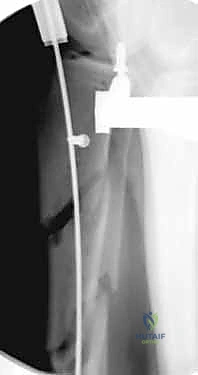

باستخدام جهاز الأشعة السينية المتحرك داخل غرفة العمليات (C-arm Fluoroscopy)، يتم سحب الساق وإعادتها لوضعها التشريحي الصحيح (Reduction) دون فتح منطقة الكسر.

بعد ذلك، يتم إدخال سلك دليلي معدني رفيع داخل القناة النخاعية، يليه استخدام أدوات توسيع دقيقة (Reamers) لتنظيف وتوسيع القناة وتجهيزها لاستقبال المسمار. هذه الخطوة بحد ذاتها تحفز نمو العظم من خلال نشر الخلايا العظمية داخل القناة.

4. إدخال المسمار النخاعي والتثبيت النهائي

يتم تمرير مسمار التيتانيوم بدقة داخل العظم. وبمجرد التأكد من موضعه المثالي بالأشعة، يقوم البروفيسور هطيف بإدخال المسامير التشابكية (Locking Screws) العرضية في أعلى وأسفل المسمار لضمان التثبيت المطلق.